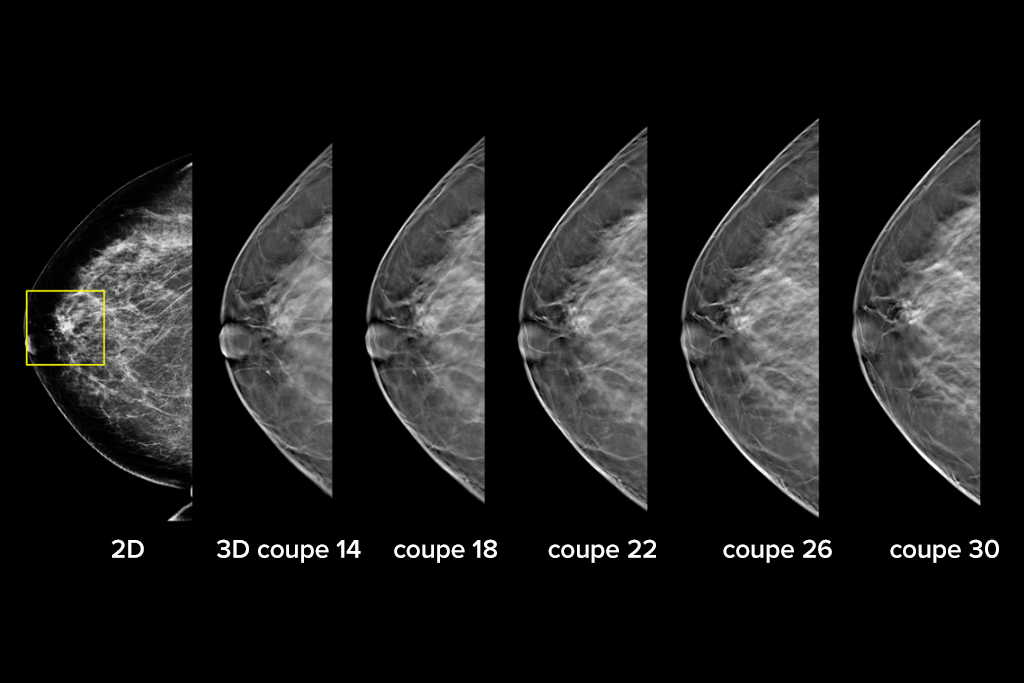

Le système Selenia Dimensions bénéficie de la précision prouvée de notre examen 3D Mammography pour détecter beaucoup plus tôt davantage de cancers invasifs du sein et diminuer les rappels par rapport à la 2D seule.2-6,*

Détectez jusqu’à 65 % de cancers invasifs en plus et réduisez les rappels de 40 % par rapport à la 2D seule.2-4,*

Une plus grande précision pour les femmes présentant des seins denses par rapport à la 2D seule.6